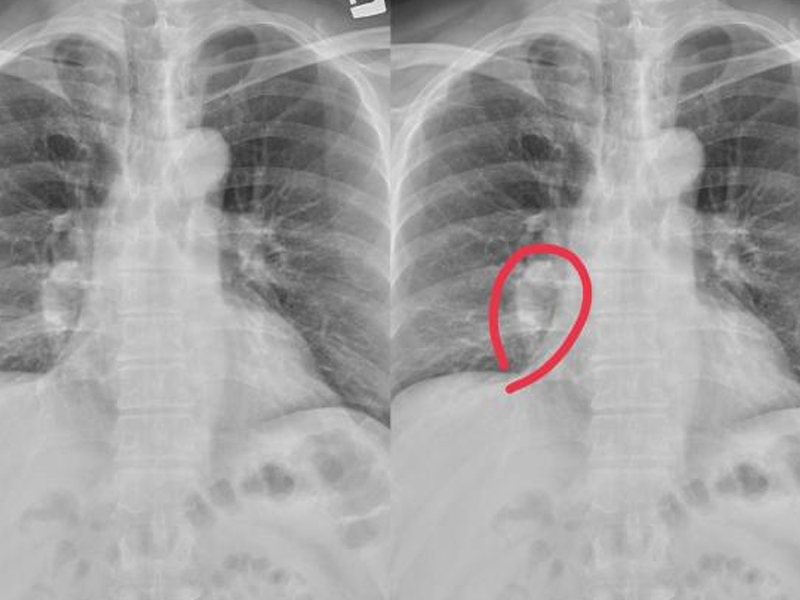

2025 年 2 月 7 日,美國麻省總醫院宣佈,外科醫生再次運用豬的腎臟,成功挽救了一名終末期腎衰患者的生命。這是麻省總醫院團隊第二次將豬腎移植到人體內。若非此次操作,醫生術前曾斷定,未來五年內這名患者的生存概率僅有 35%。

66 歲的患者蒂姆・安德魯斯(Tim Andrews)在術後僅一周就出院了,且此後無需再接受透析。

與魯尼不同的是,安德魯斯接受的腎臟來自美國生物科技公司 eGenesis,這頭豬共進行了 69 處的基因編輯,其中 59 處用於滅活豬內源性逆轉錄病毒(PERV),其餘則用於避免排斥反應等。

安德魯斯的手術在 1 月 25 日進行,美國兩家製藥公司也為他提供了最新的藥物,抑制免疫系統,最大程度降低異種器官的排斥風險。

「手術歷時 2.5 小時,移植的豬腎在 10 分鐘內就開始產生尿液。」Tatsuo Kawai 教授介紹,「一切都非常順利,他狀況良好,沒有出現任何併發症。」

目前,安德魯斯已經出院,但未來一段時間,他仍需接受持續的醫療監測,每周返回醫院進行血液檢查。此外,他還攜帶多種遠程設備,以便臨床團隊可以實時檢查他的生命體徵和心律。